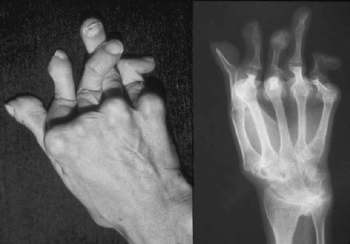

53.1.1. Rheumatoid arthritis

Reggeli ízületi merevség.

Három vagy több ízületi régió gyulladása.

Kéz ízületeinek gyulladása.

Szimmetrikus ízületi érintettség.

Rheumatoid csomók jelenléte.

Radiológiai elváltozások (juxtaarticularis porosis vagy marginális erosiók)